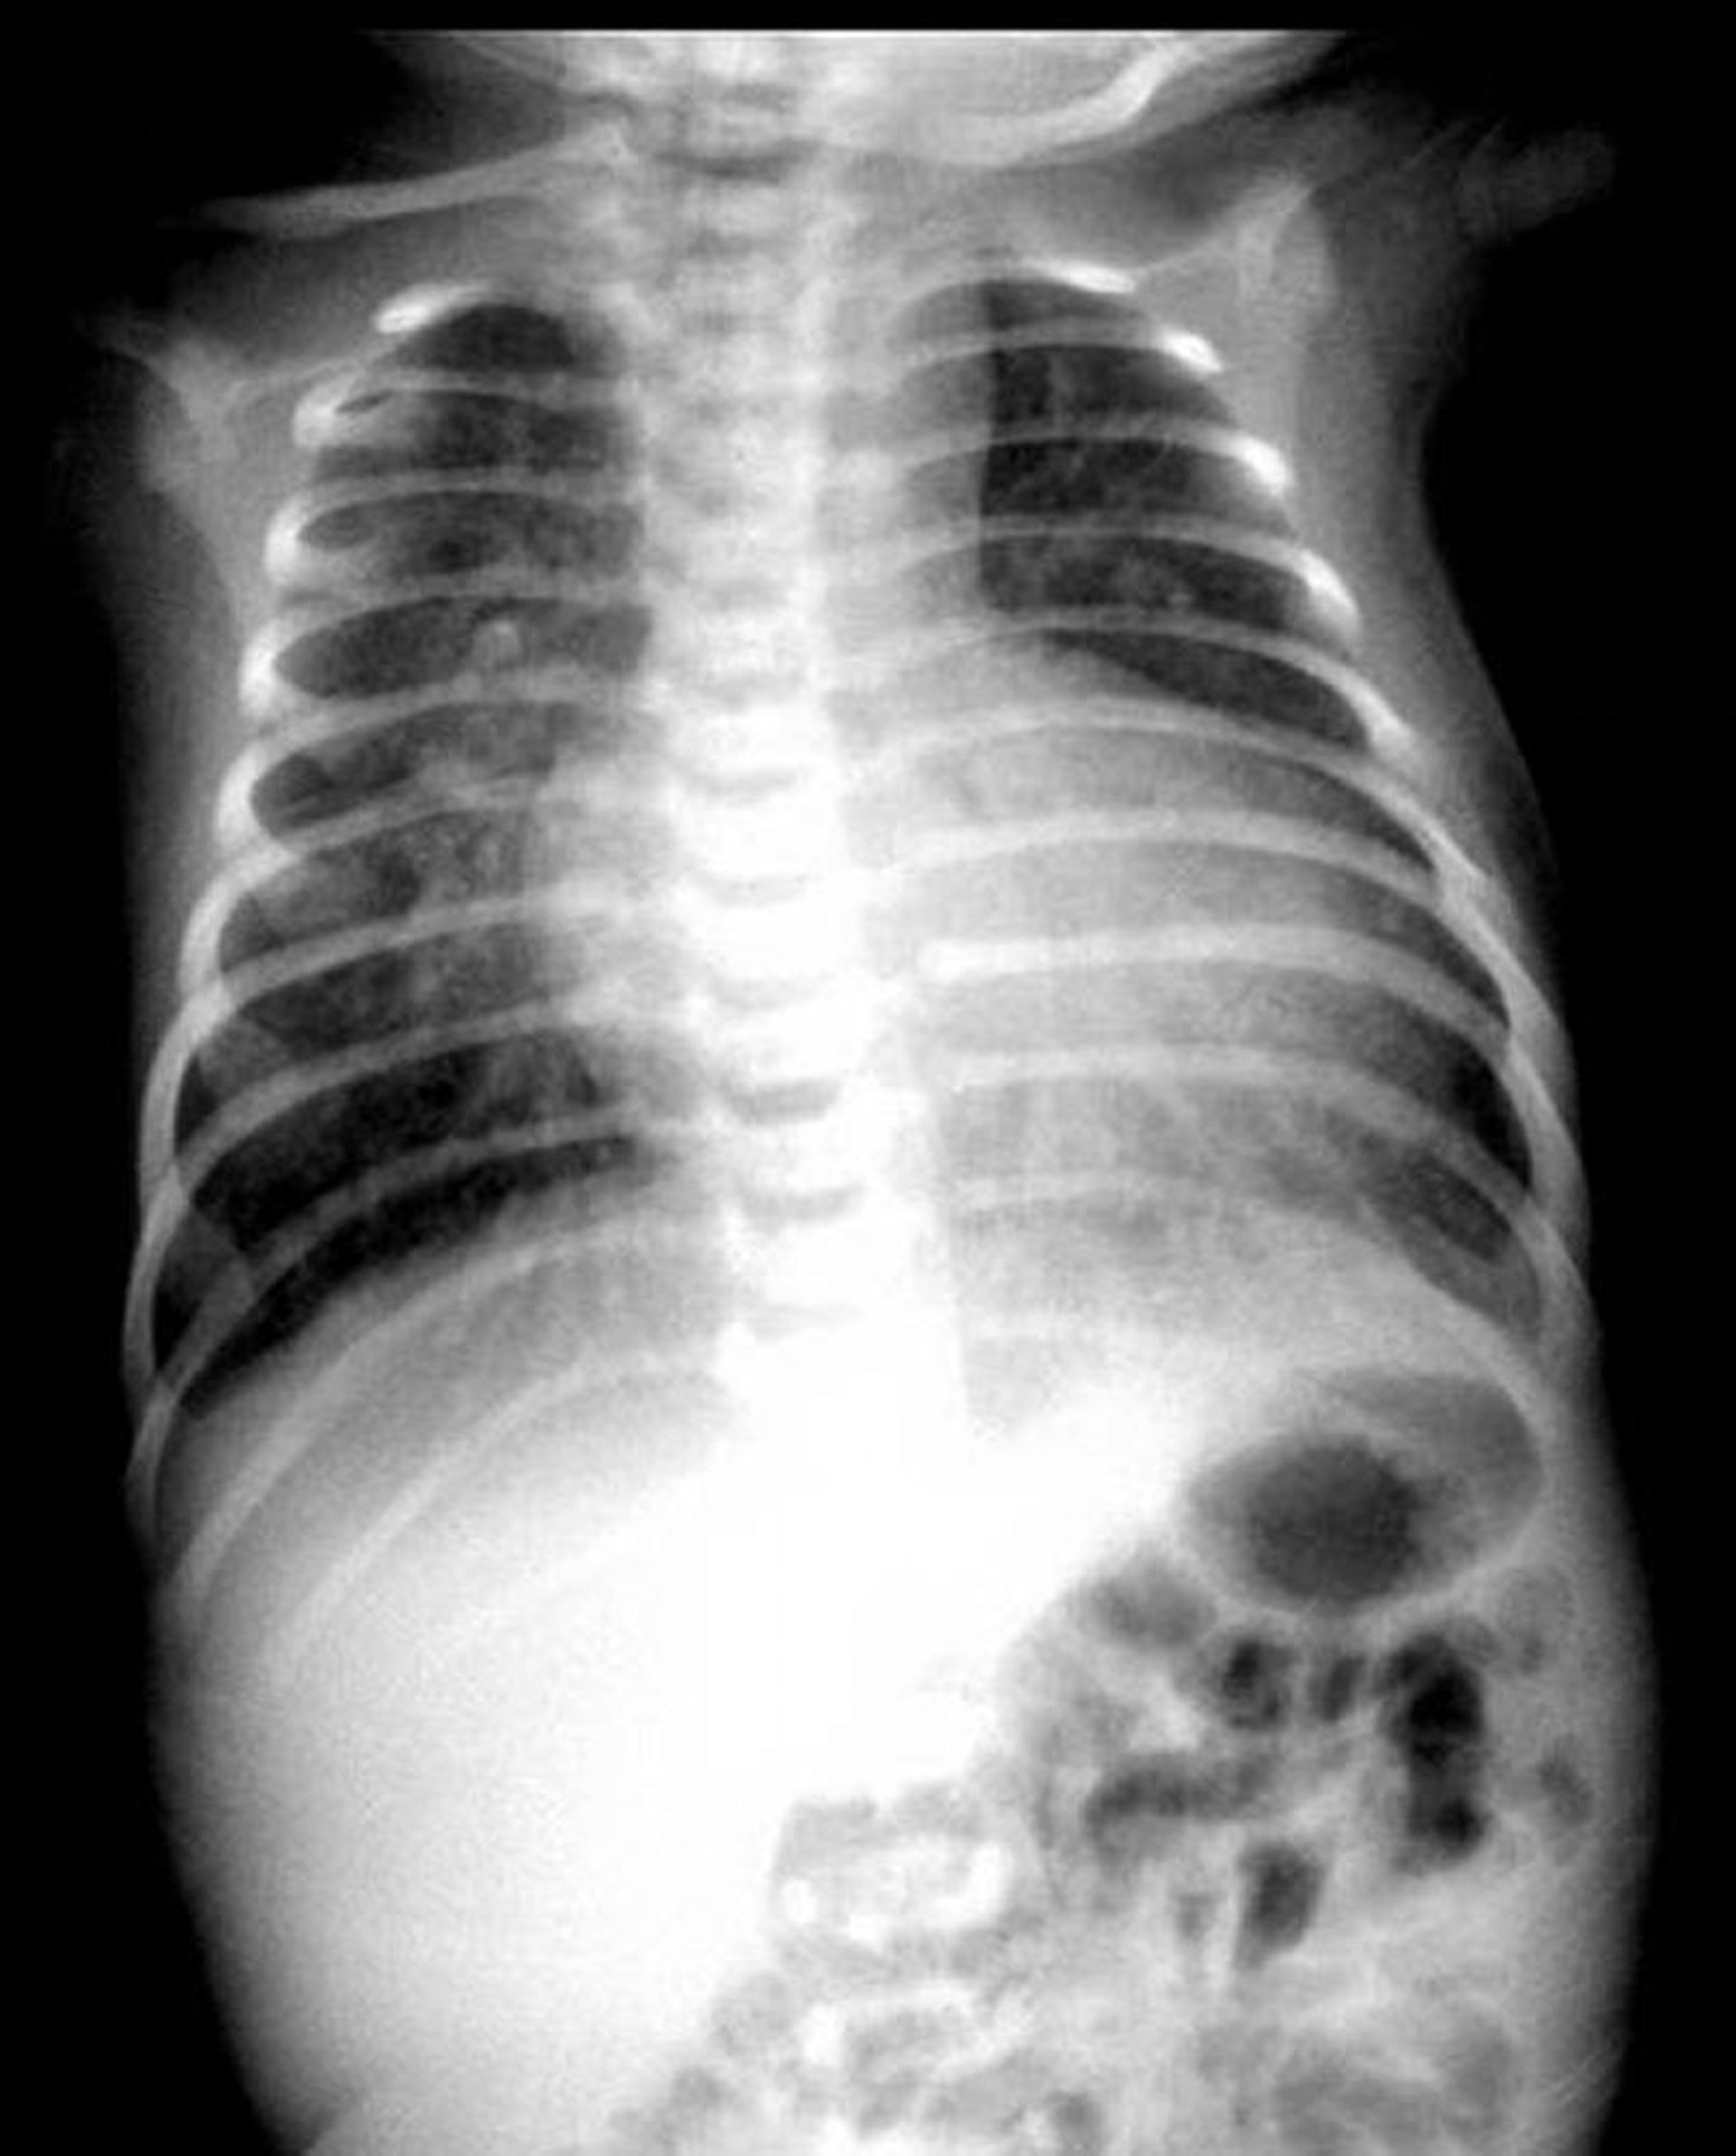

Rx thorax montrant l'aspect classique d'un œuf-sur-un-fil chez un patient présentant une transposition des grandes artères.

Image fournie par Jeanne Marie Baffa, MD.